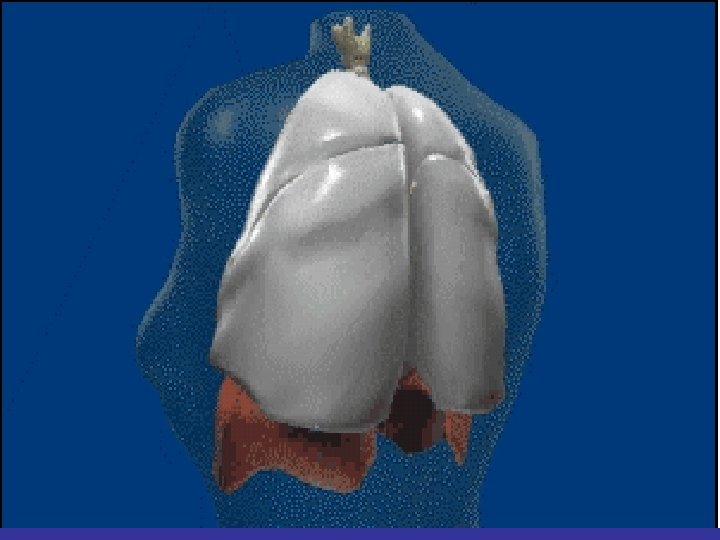

Lobes and Fissures

lateral view ? ! can detect otherwise hidden masses